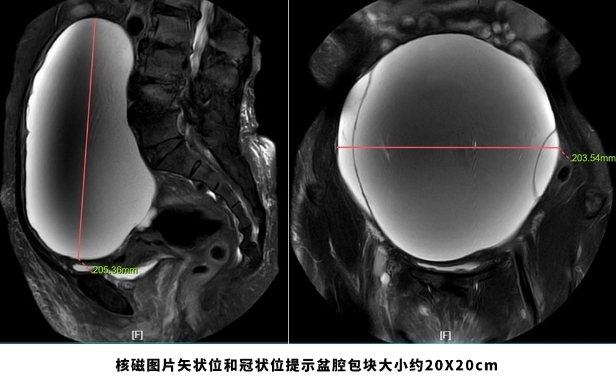

新浪微博网页版:69岁老妇挺着“大肚子”来医院,检查后竟“怀”了个巨大肿瘤!